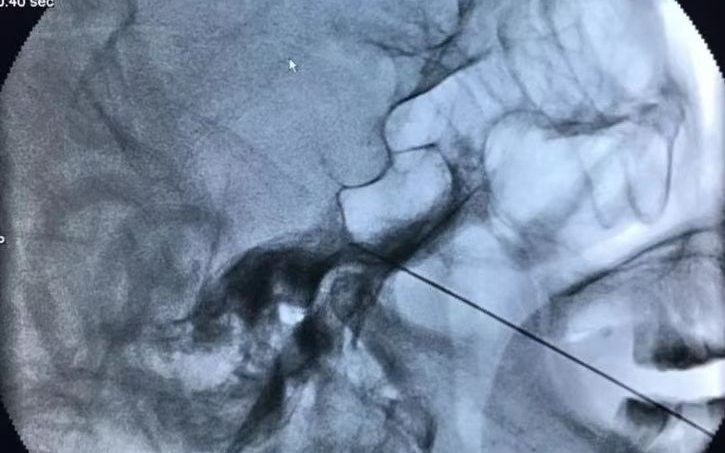

射頻神經(jīng)毀損術(shù)干預(yù)三叉神經(jīng)痛,是在X射線和CT引導(dǎo)下將射頻針經(jīng)皮刺入三叉神經(jīng)節(jié)處,選擇性破壞傳導(dǎo)痛覺、溫覺神經(jīng),達(dá)到止疼效果,適用于年老體衰有系統(tǒng)疾病,不能耐受手術(shù)者。

? 定位準(zhǔn)確:在C型臂或CT下精準(zhǔn)定位,射頻針直接作用在病變神經(jīng)上,數(shù)據(jù)精確到1毫米以下,角度誤差小于1度,且僅對病變神經(jīng)進(jìn)行處理。

? 微創(chuàng):射頻針不足1毫米,如同一根針灸針,所以創(chuàng)口只有1毫米,過程幾乎不出血,干預(yù)精確。